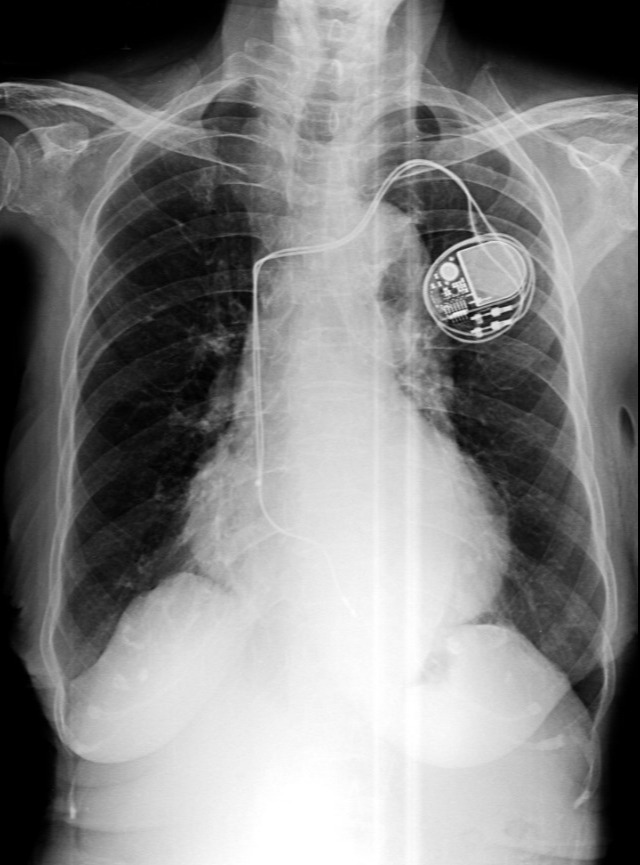

Pacemaker Treatment in Pune for Steady Heart Rhythm Support